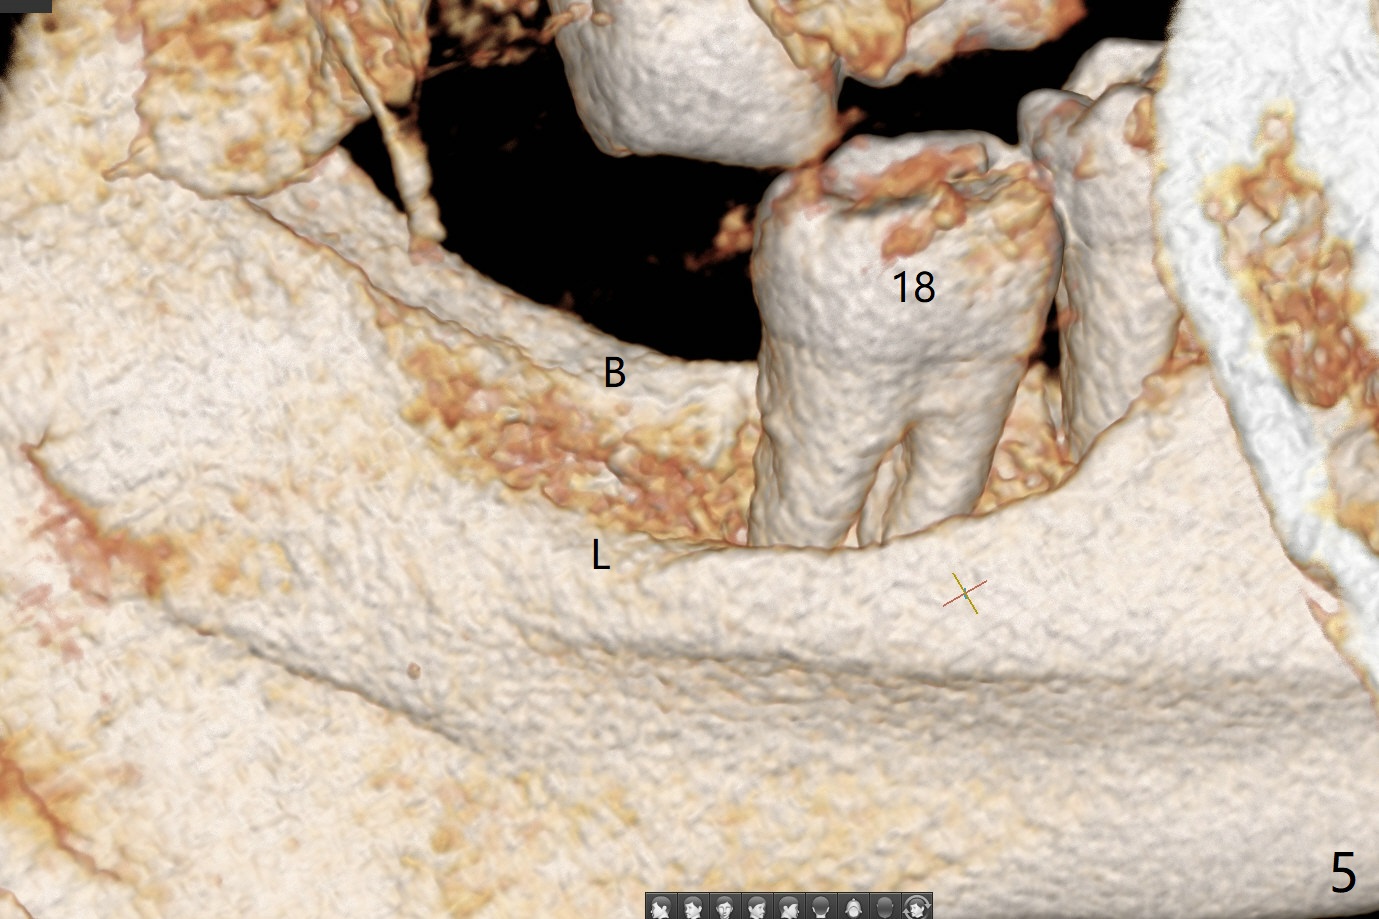

55岁男13年前就诊深洗同时拔除左下智齿(第二第三磨牙之间无骨,图一),拔除后没有植骨。十年后第二磨牙远中出现骨缺损(图二),十三年后第二磨牙松动(图三),需要拔除种植(图四)。其实当年拔除后必须植骨(图一’:红色 (白色:膜或者塞)),甚至种植(图一”:绿色),植骨。Thirteen years post #17 extraction, the lingual plate (L) is lower than the buccal one (B). Return to Prevent Molar Periimplantitis (Protocols, Table) No Caries No Antibiotic Plug 提升 手术 Xin Wei, DDS, PhD, MS 1st edition 03/27/2021, last revision 05/31/2021